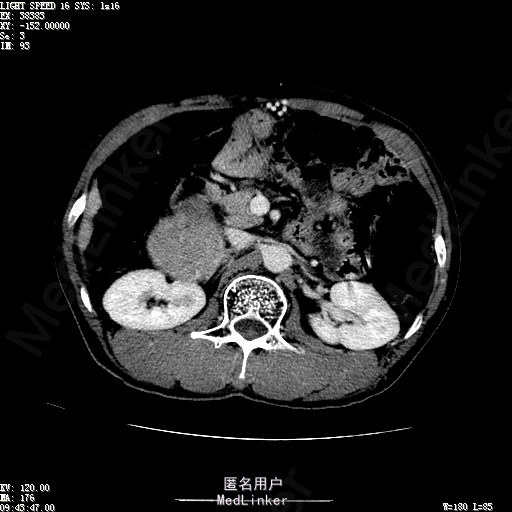

查体:体温36.4℃,脉搏76次/分,呼吸18次/分,血压110/70mmHg。神志清晰,发育正常,营养中等,体位自如,表情安静,慢性病容,检查合作。皮肤粘膜颜色正常,无瘀点、紫癜,有肝掌,无蜘蛛痣,无水肿,毛发的生长与分布正常。浅表淋巴结浅表淋巴结未触及肿大。无巩膜黄染,结膜正常。口唇红润,粘膜正常,舌正常,牙龈正常,扁桃体无肿大,无咽部充血。颈部外形对称,颈静脉正常,肝颈静脉回流征阴性,气管居中。甲状腺正常,无颈部血管杂音。胸部形态正常,呼吸运动平稳规律,无呼吸困难,肋间隙正常。触诊语颤正常,无胸膜摩擦感,肺下界位于右锁骨中线第六肋间。呼吸音正常,未闻及干湿啰音,无胸膜摩擦音。无心前区隆起,心尖搏动正常,心率:76次/分,心律齐,心音正常,无杂音,无心包摩擦音。无大动脉及周围血管征,无奇脉及交替脉,无水冲脉,无枪击音,腹型对称,无腹壁静脉曲张,未见胃肠型及蠕动波,无瘢痕,脐部正常。无压痛,无反跳痛,无腹肌紧张,无腹部包块。肝未触及,Murphy征阴性,脾未触及,肾未触及,无移动性浊音。无肝区叩击痛,无肾区叩击痛,无脾区叩击痛。肠鸣音正常4次/分,无气过水声。外阴及肛门:未查。四肢正常,关节正常,无下肢水肿,无下肢静脉曲张,无杵状指趾。 辅助检查:彩超:肝表面欠光滑,肝内占位5.2*5厘米 ct如下图

诊断:乙肝肝硬化 代偿期 原发性肝癌。 患者病史明确,目前化验转氨酶轻度升高,说明有活动性肝损伤,白蛋白降低提示肝脏合成代谢功能下降,AFP从一年前至今逐渐升高,提示活性肿瘤细胞增多。CT所见明确诊断肝癌,并有周围卫星灶,应近期行TACE治疗。 处置:DSA下肝动脉造影及TACE 手术简要经过:患者平卧位,术区皮肤消毒,铺手术巾,2%利多卡因局麻后,Seldinger法穿刺右股动脉,入血管鞘,5F猪尾管腹主动脉造影,超滑导丝yidao5F RH管腹腔干、肠系膜上动脉、左肾动脉分别造影,腹腔干造影时,见肝右叶7-8处小结节样肿瘤染色,未见外凸生长较大病灶染色。微导管超选肝右动脉注入三氧化二砷碘油混悬液10毫升,横结肠遮挡部位见较大病灶有伞状碘油沉积。复查造影未在见肿瘤染色,拔出导管和血管鞘,穿刺处压迫止血,加压包扎。术毕。

患者术后8天来,无不适,无发热,无腹痛和腹胀,无恶心呕吐,食欲睡眠好,尿便正常。 查体:神志清,巩膜无黄染,心肺听诊无异常,腹软,无压痛,肝脾肋下未触及,移动性浊音阴性,双下肢无浮肿。 复查化验结果:丙氨酸氨基转移酶 116 U/L、天门冬氨酸氨基转移酶 41 U/L、胆碱酯酶 1995 U/L↓、总蛋白 56.3 g/L、白蛋白 25.9 g/L。白细胞计数 5.8 10^9/L、红细胞计数 3.18 10^12/L、血小板计数 175.0 10^9/L、*血红蛋白 83 g/L、血小板分布宽度 15.7 、血小板压积 0.175 %、*红细胞压积 24.6 %、平均红细胞血红蛋白 26.1 pg、平均红细胞血红蛋白浓度 337.0 g/L、平均红细胞体积 77.5 fL、平均血小板体积 10.0 fL、嗜碱性粒细胞百分比 0.4 %、嗜碱性粒细胞数量 0.02 10^9/L、中性粒细胞百分比 70.4 %、中性粒细胞数量 4.10 10^9/L、嗜酸性粒细百分比 2.1 %、嗜酸性粒细胞数量 0.12 10^9/L、单核细胞百分比 12.2 %、单核细胞计数 0.7 10^9/L、淋巴细胞数量百分比 14.9 %、淋巴细胞计数 0.9 10^9/L。甲胎蛋白 23564.00 ng/mL 患者术后第8天开始行FOLFOX6化疗。CT上可见明显碘油沉积,术后甲胎蛋白下降治疗有效。嘱患者术后必须定期复查